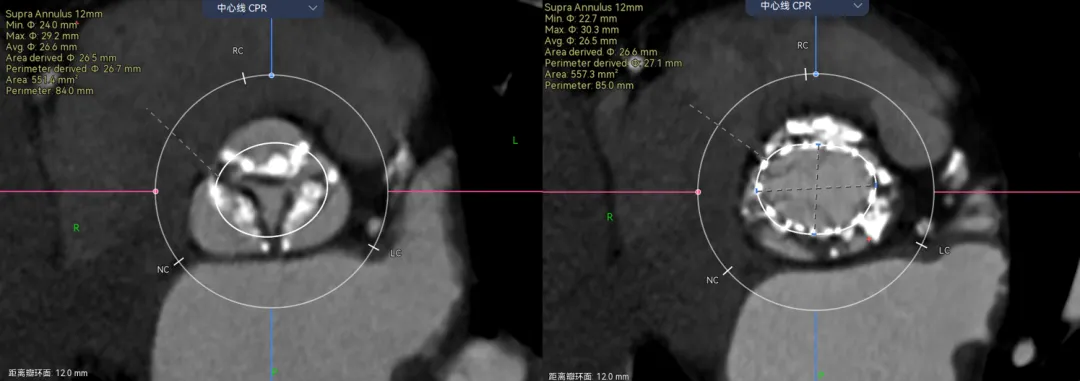

看大小:对你画的圈大概在那个位置心里有数以后,就涉及到圈画多大了,这里我都是一个原则,就是我画圈是为了看限制区域有多大,然后根据限制区域来看我的oversize值。除非看冠脉风险我才会根据瓣膜的参数,预估的植入位置来算这个平面的SIMU大小。

举个例子,病例-5,Type1的单边钙化,延伸到LVOT,瓣环这里笔者认为是因为把钙化避开的,因为他会对瓣膜有推挤作用。有些人则不会避开,这样瓣环会比预估的要大很多。

画法1-把钙化圈进去,瓣环径28。画法2-避开钙化,瓣环预估26.3,相差接近2mm。

那么这两种画法会对瓣膜型号选择造成很大的误判么?答案是不会,因为这个病人的限制在瓣上,你只能根据瓣上的空间来oversize,而且预估肯定会有点儿漏。

在看这个病例,三页瓣,RN、LR都有点融合。先看位置,融合会把瓣膜往左右交界的地方挤一挤。

再来看瓣上,你会发现我画的瓣上比真实的要大。这里就涉及到瓣膜的锚定区域了,我预估的瓣上如果瓣叶打开可能会是直径在25mm左右,但是真实瓣膜的尺寸如果在这个位置,他只有22左右。所以瓣上是没有办法提供锚定的,只能卡在瓣环。

可以看到,瓣膜放进去23的区域正好对应该型号瓣膜尺寸。